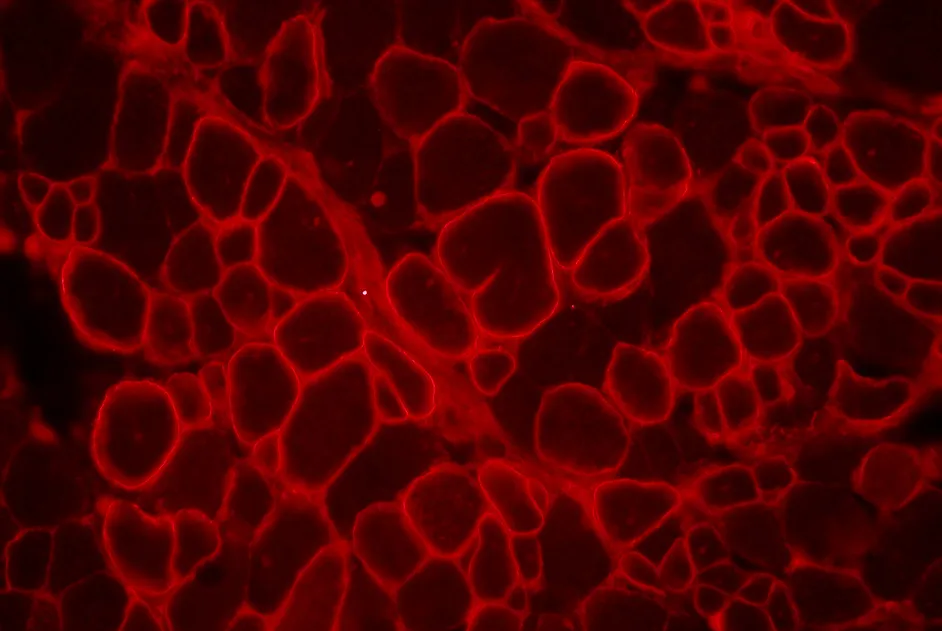

Myasthénie autoimmune : les autoanticorps anti-LRP4

Identification de nouveaux auto-anticorps anti-LRP4 dans le sérum de 13 patients atteints de myasthénie auto-immune séronégative